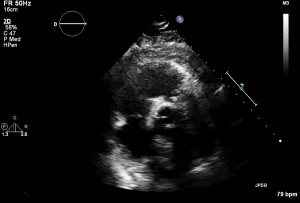

- TTE shown 1 day prior to pulmonary valve replacement

- Severe PS with max velocity 4.6m/s and mean gradient 84.6mmHg

- Moderate PR

- Mod-Severe RV dysfunction

- Carcinoid involvement of pulmonic valve classically showed thickened valve with restricted motion

Thank you Dr. Dias and Diamantouros for the case.